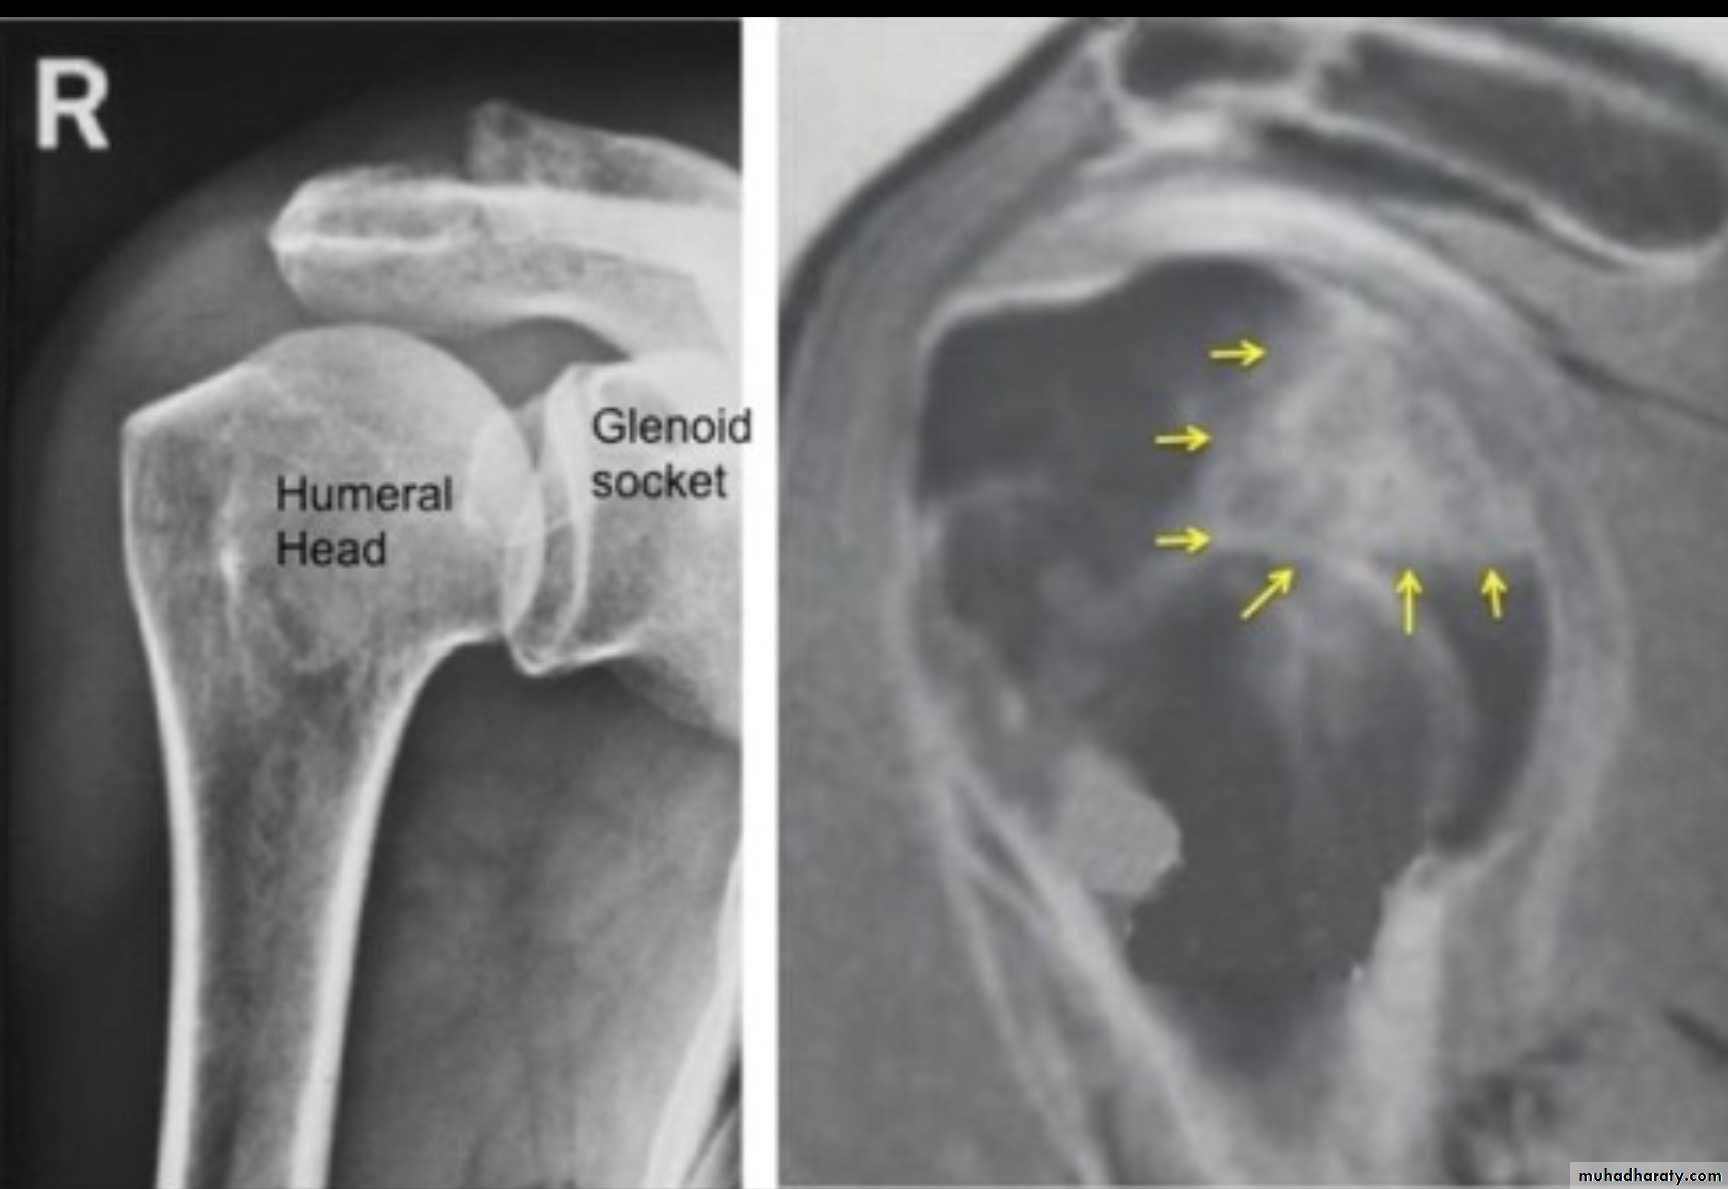

X RAY

MRI